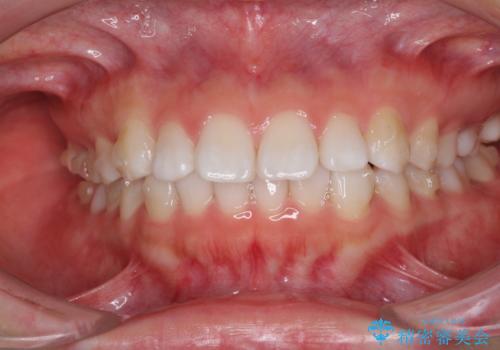

インビザラインによる軽度な出っ歯の矯正治療

- 上の前歯の出っ歯を治したいとのことで来院された患者様です。

上下顎ともにIPR(歯と歯の間を削る)と歯列全体の拡大によって口元が引っ込むように設計し、インビザラインにより治療を行うこととしました。

どこまで口元を引っ込めることができるのか、患者様自身も正直分からない部分があったため、少しずつ治療ゴールを変更しながら仕上げていきました。

気になっていた前歯の飛び出した印象は、最終的にはスッキリと引っ込み、大変満足していただきました。